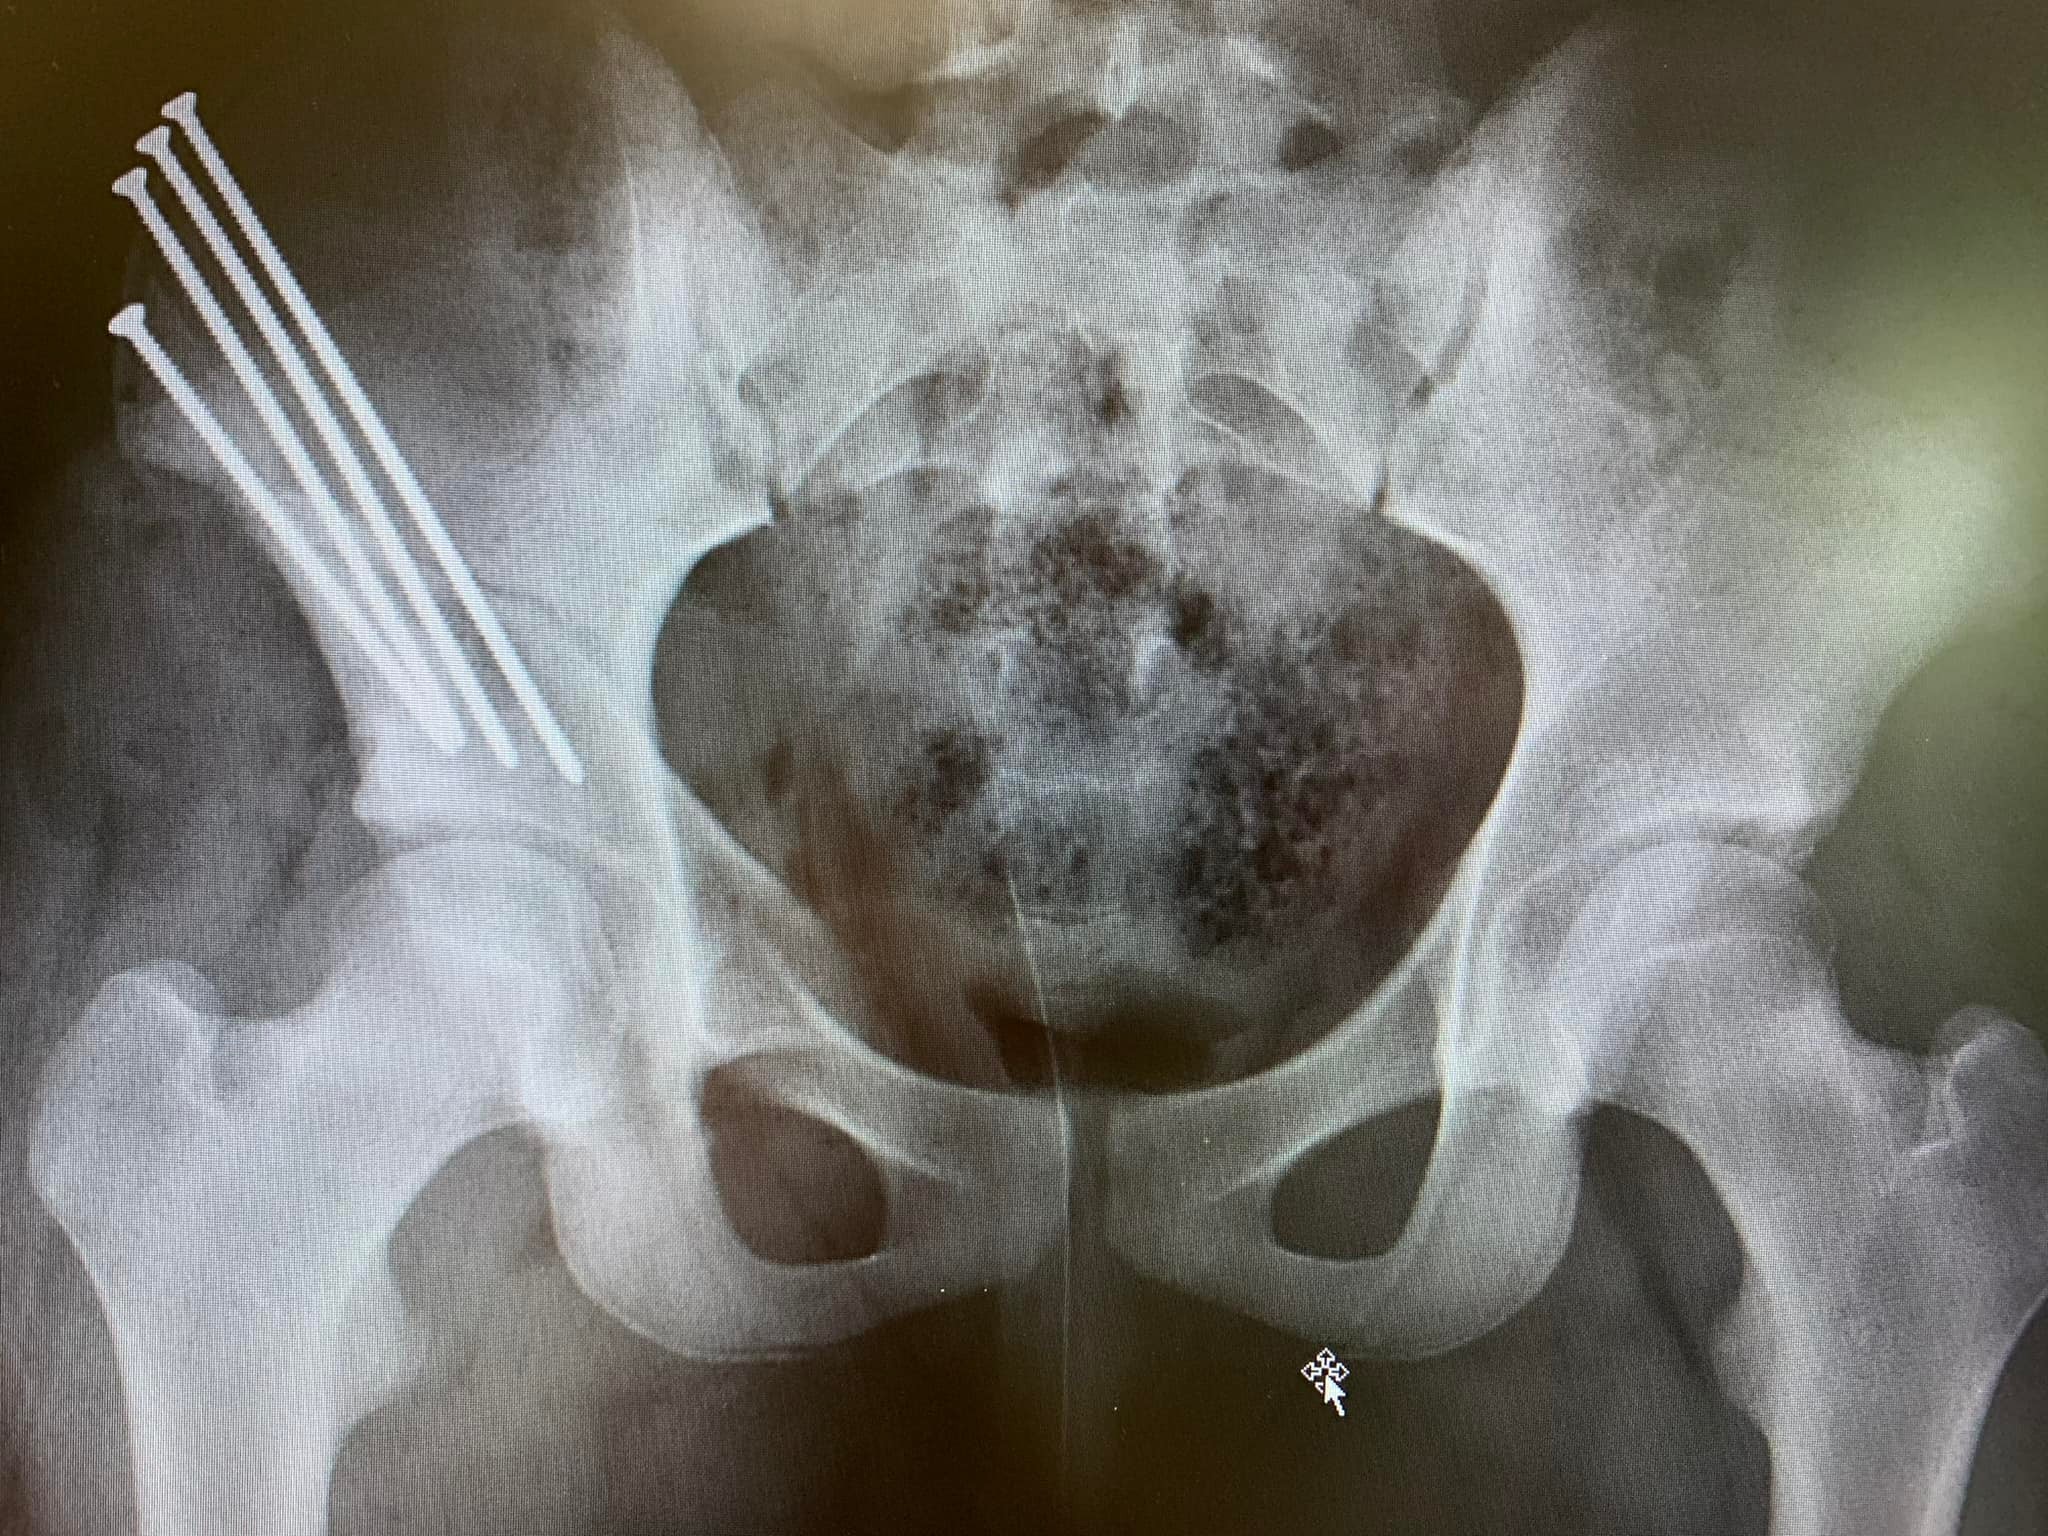

Skylin had hip surgery on April 25th and went home on April 27th. She is doing great. By all early indications, her hip surgery was a success. She had some fun visitors, including 2 week old Shawn Fletcher. She will have a long (6 month) recovery, but is ready to attack PT and get back to her normal routine. Skylin is going home with a wheelchair, walker and crutches. She cannot be weight bearing (at all) for several weeks. As you will see in the picture below, she has some serious screws that will be in her right hip forever. No more metal detectors at TSA.